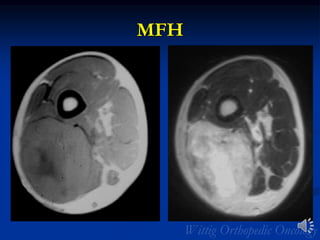

MFH

Radiology

Malignant Fibrous Histiocytoma

• Deep intramuscular mass (often adjacent to

diaphysis of long bones)

• Osseous involvement can occur (Xray or CT)

• MRI:

• Heterogeneous T1 and T2/large/lobulated/well-

defined

• Necrosis and hemorrhage

• Intermediate SI on T1

• Predominantly high SI on T2

• Viable areas enhance with contrast

• Peripheral pseudocapsule misleading

• Circumscribed appearance

• Myxoid variant very high signal on T2

• Myxoid variant may show peripheral and septal

or diffuse enhancement

• Look for fat to r/o liposarcoma